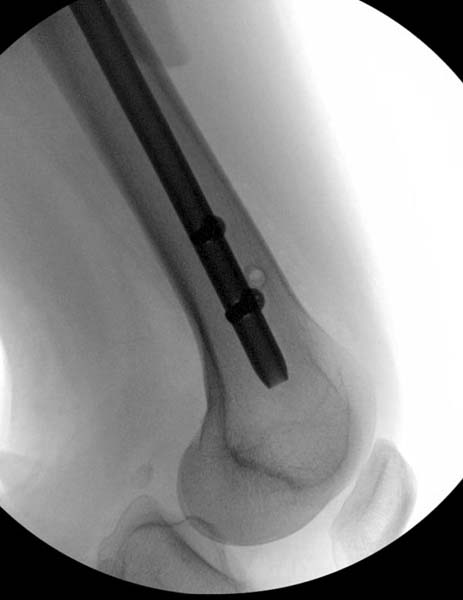

> стабильная.. На третьий день провели стабилизацию перелома бедра

> антеградным остеосинтезом.

> Закрытый БИОС решает множественные проблемы связанные с лечением

> переломов, но проблема дистальной блокировки без рентгена до сих пор

> Для решения проблемы дистальной блокировки компания DigiMed недавно

> предложила систему блокировки без рентгена. Пока в стране только два набора

> и только для антеградных гвоздей, но компания работает над созданием

> устроиства для других гвоздей тоже..

> Результат первых случаев показала отсутствие разницы между занятиями на

> муляжах, а также Workshop и с удивительной точностью вывел латерально над

> кожей специальное сверло. Дальше по сверлу тонкий направитель и проводится

> сверление каннюлированным сверлом....